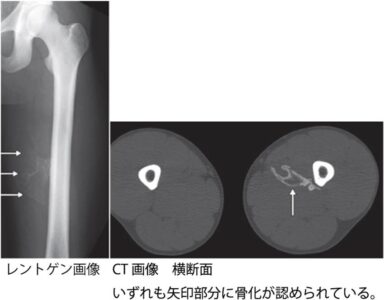

打撲後の骨化性筋炎について

強い打撲や筋肉内の出血が原因で、後日、筋肉組織内に骨のような塊が形成されることがあります。しこりを触れるようになり、動かすと痛みが生じることが特徴です。